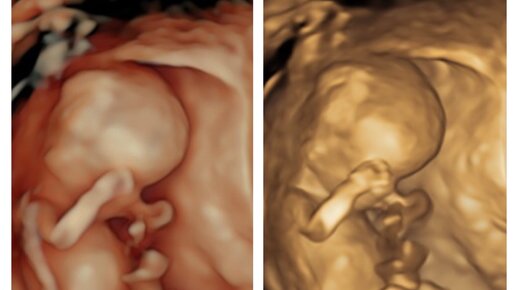

Первый скрининг в КЛИНИКЕ САРЕНКО